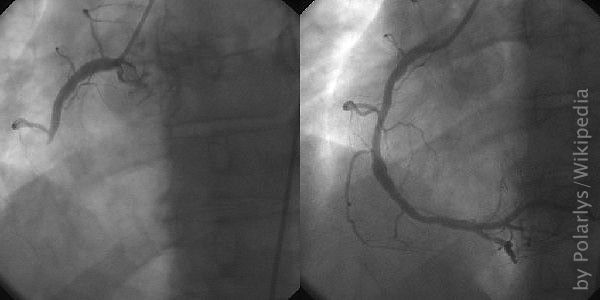

Herzensangelegenheit Gefaesse Dd

Tauchen – eine Herzensangelegenheit

Im März 2016 macht sich der 55-jährige Stefan R. aus der Nähe von Mannheim zusammen mit seiner Lebensgefährtin Patricia auf den Weg nach Java, Indonesien. ... Weiterlesen